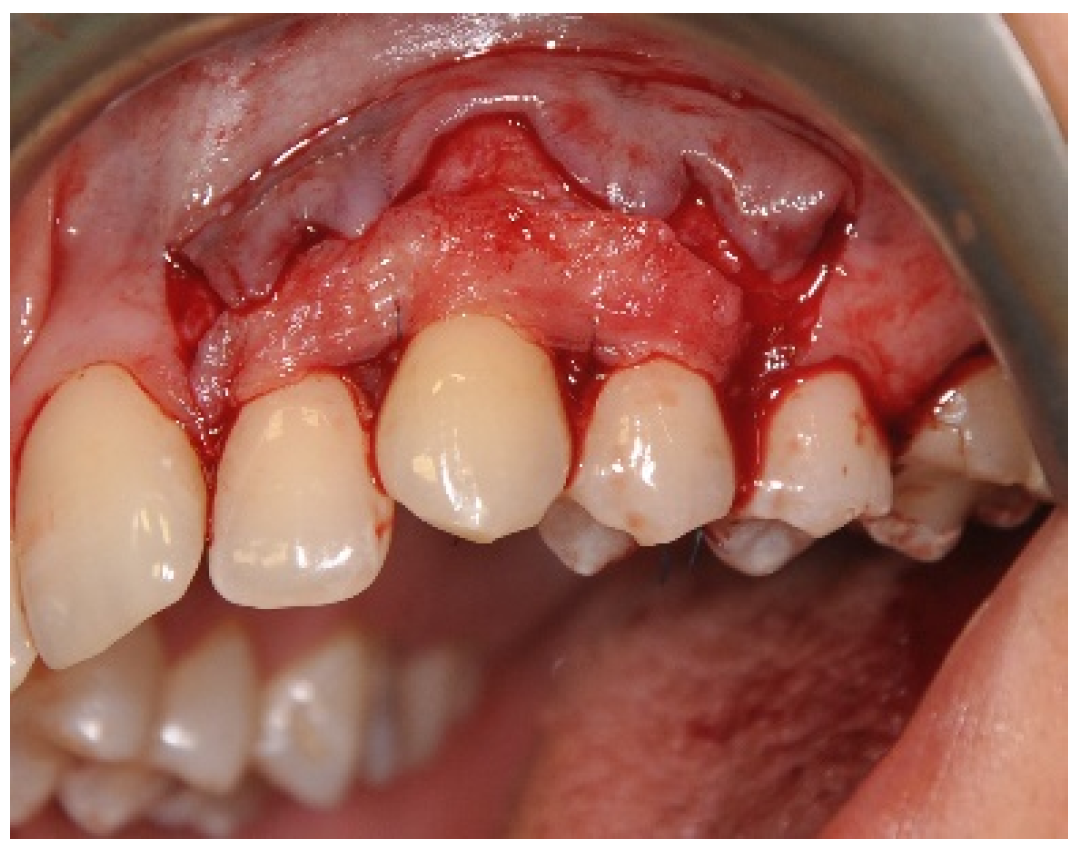

2.3. Surgical Procedures

3.1. Clinical Measurements for CAL and GRD

3.2. Clinical Measurements for GRW, PD and AG